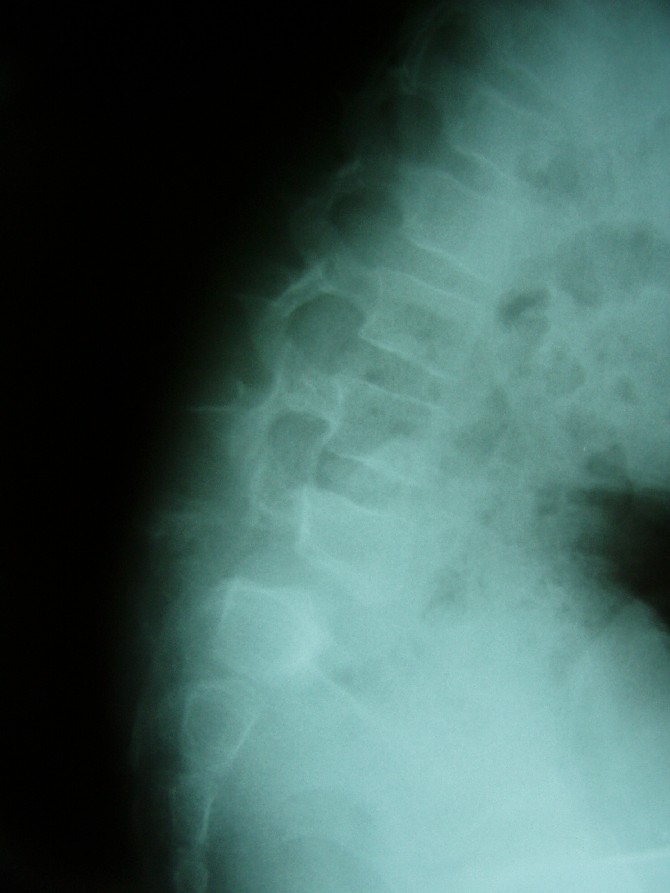

7 yaşında kız hasta duruş bozukluğu, bel çukurunda artış ve ara sıra olan bel ağrısı şikayeti ile başvurmuştu.

İncelemelerde L5-S1 omurlarında hereketli bel kayması olduğu saptandı. Bu kaymanın nedeni doğuştan olan ve omurgayı yerinde tutatn bazı kemik köprülerin olmayışı idi.